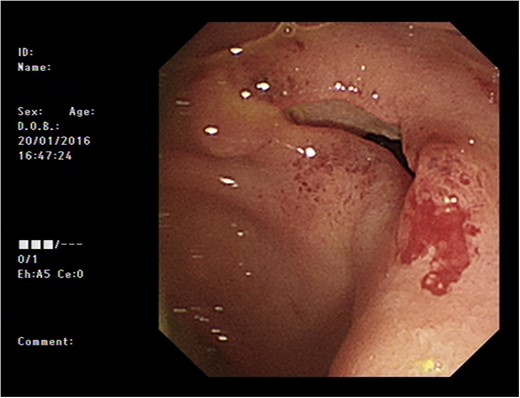

Initial upper GI endoscopy failed to enter the duodenum due to residue within the stomach with the appearance and odour of faeces noted. Abdominal computed tomography (CT) suggested a cavity with adherent ileum adjacent to the second part of the duodenum (Fig. 1). A contrast study was then undertaken demonstrating rapid flow of contrast into the terminal ileum and caecum originating from the duodenum (Fig. 2). Repeat upper GI endoscopy demonstrated an abnormal fungating fistulous communication between the duodenum and terminal ileum which permitted the full insertion of the endoscope (Figs 3 and 4). Biopsies were consistent with diffuse B-cell lymphoma (DLBCL) in accordance with the WHO classification.